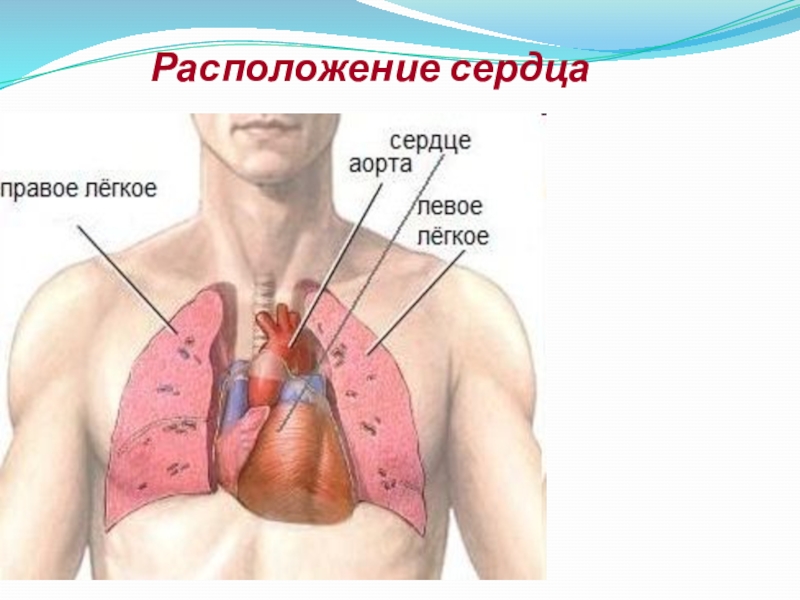

Сердце у человека располагается в грудной полости.

Расположение сердца у человека.

Анатомическое расположение сердца.

Сердце в грудной клетке расположено.

Где расположено сердце у человека анатомия.